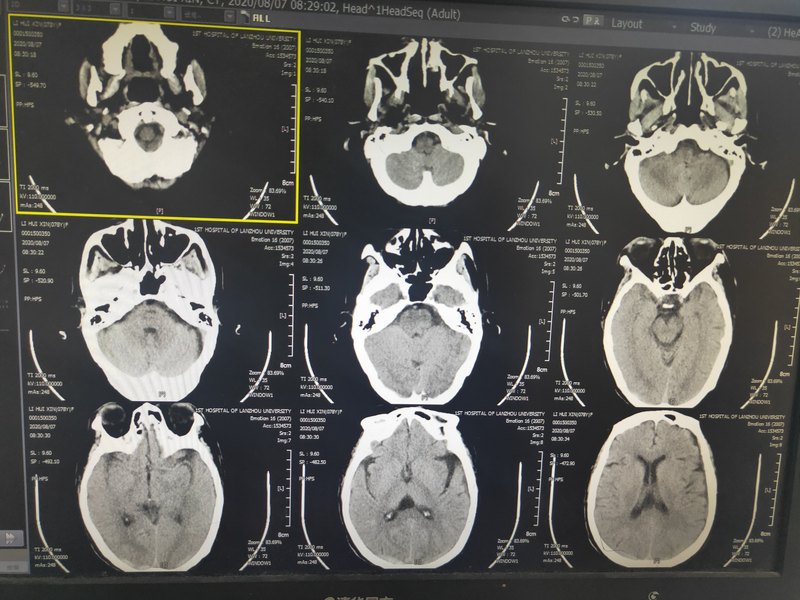

慢性硬膜下血腫的概念: ●血腫的位置一硬腦膜 與蛛網(wǎng)膜之間。 ●血腫的特點一一是 具有包膜的血腫。 ●血腫開始出現(xiàn)癥狀的時間一- 超過3周。 ●血腫的CT表現(xiàn)特點一一各 種密度均可出現(xiàn)(低密度,或等密度,或高密度,或混雜密度),成新月形。

硬腦膜外血腫約占外傷性顱內(nèi)血腫的30%,大多屬于急性型??砂l(fā)生于任何年齡,兒童少見。其CT特點為在顱骨內(nèi)板下方有雙凸形或梭邊形,可見占位效應(yīng),中線結(jié)構(gòu)移位,病變處腦室受壓,變形和移位。硬腦膜下血腫是發(fā)生于硬腦膜與蛛網(wǎng)膜的血腫,是顱腦損傷常見的繼發(fā)性損害,好發(fā)于額部,顳部以及腦底部。CT表現(xiàn)為顱骨內(nèi)板下方新月形高密度區(qū),也可見同樣的占位效應(yīng)。王曉強(qiáng)主任專家門診時間:周四上午,周四下午地址:上海市楊浦區(qū)控江路1665號新華醫(yī)院28號樓兒科綜合樓4層王曉強(qiáng)主任特需專家門診時間:周二上午。地址:上海市楊浦區(qū)控江路1665號新華醫(yī)院28號樓兒科綜合樓5層

今天的第一臺手術(shù)是一位八十歲的老大爺,來自黑龍江佳木斯,在林場工作,到佳木斯也需要3個小時的時間。身體一向很好,可以說是:眼不花,耳不聾,健步如飛。近兩個多月前有一次不經(jīng)意的頭部受傷時,當(dāng)時沒有任何不適,也沒有任何治療。7月29日,病人因為頭痛查頭顱CT發(fā)現(xiàn)慢性硬膜下血腫(圖1),在當(dāng)?shù)蒯t(yī)院做了鉆孔引流(圖2),病人的頭痛癥狀也改善了。近一周病人頭痛癥狀明顯加重,而且出現(xiàn)右側(cè)肢體的無力,復(fù)查CT發(fā)現(xiàn)血腫復(fù)發(fā)了,而且明顯的增大了(圖3~5)。立即從佳木斯經(jīng)過十幾個小時的時間才來到了北京,今天的手術(shù)非常順利,剛剛看過病人意識狀態(tài)明顯改善,頭痛消失,語言對答流利,而且肢體活動也恢復(fù)了正常。慢性硬膜下血腫多發(fā)生于老年人,可能與腦萎縮有關(guān),如果病人出現(xiàn)頭痛,意識變差,一側(cè)肢體偏癱,不要以為就是腦梗了,要及時的檢查CT或核磁共振,早明確診斷早治療效果會更好。

臨床中多數(shù)慢性硬膜下血腫鉆孔清洗血腫可以解決。但少數(shù)需要開顱清除血腫。這就需要術(shù)前做頭顱MR明確血腫是否信號不均質(zhì)。術(shù)前CT可以看到左側(cè)大腦半球表面血腫密度不均勻,有高有低,需要做核磁進(jìn)一步明確。核磁顯示左側(cè)大腦半球表面血腫信號不均勻,考慮有固態(tài)的血塊存在,鉆孔可能無法清洗滿意,這時可以考慮開顱清除血腫。

臨床門診經(jīng)常能見到肢體乏力或者癡呆表現(xiàn)的患者,起初收治神經(jīng)內(nèi)科,拍片子(CT或MR)發(fā)現(xiàn)一側(cè)或者雙側(cè)硬膜下血腫,多數(shù)這類病人可以追溯問到近期有過頭部外傷史。一般這類患者多以老年人常見,頭部外傷后首先可以看到硬膜下積液,如不注意一二個月后部分可以進(jìn)展為慢性硬膜下血腫。CT表現(xiàn)為右側(cè)半球等密度信號,將右側(cè)半球壓迫到左側(cè),右側(cè)腦組織表面腦溝腦回顯示不清,同時左側(cè)顯示為硬膜下積液。如果血腫不多,容易從CT片子上漏診,這需要MR進(jìn)一步檢查MR顯示的就很清楚了,右側(cè)半球硬膜下血腫了。這種慢性硬膜下血腫一般多數(shù)顯示信號均勻,可以鉆孔清洗血腫解決。